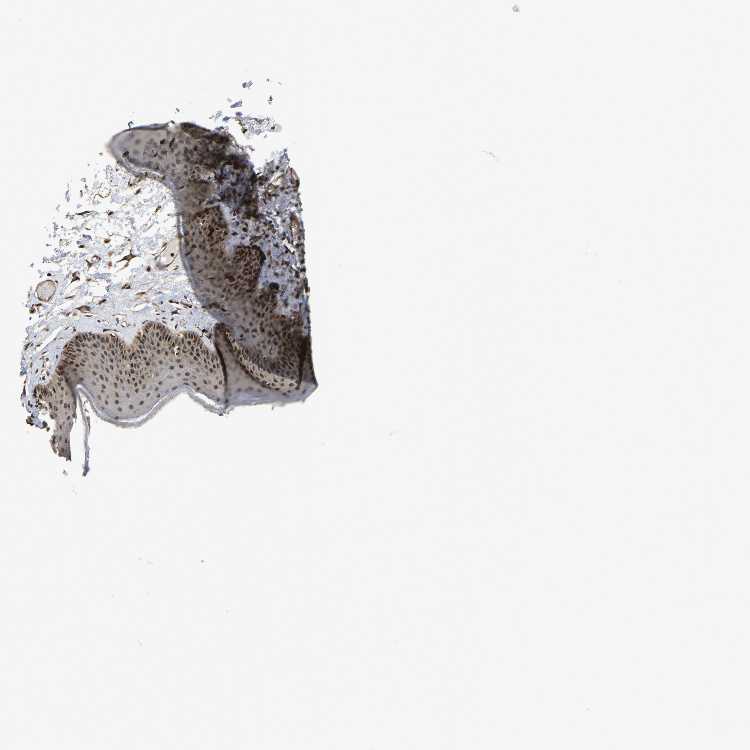

SKIN 1 - Antibody stainingi

Antibody staining in the annotated cell types in the current human tissue is reported as not detected, low, medium, or high, based on conventional immunohistochemistry profiling in selected tissues. This score is based on the combination of the staining intensity and fraction of stained cells.

Each image is clickable and will lead to virtual microscopy that enables deeper exploration of all samples and also displays staining intensity scores, fraction scores and subcellular localization as well as patient and tissue information for each sample.

Antibody HPA017882

Langerhans Medium

Fibroblasts High

Keratinocytes Medium

Melanocytes Medium

SKIN 2 - Antibody stainingi

Epidermal cells High